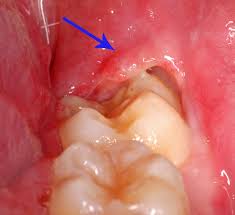

Η περιστεφανίτιδα είναι μια φλεγμονή των μαλακών ιστών γύρω από ένα ημιέγκλειστο δόντι και η συνηθέστερη εντόπισή της είναι οι τρίτοι γομφίοι της κάτω γνάθου (φρονιμίτες). Η ανατολή των δοντιών αυτών γίνεται ιδιαίτερα αργά, ιδίως όταν επηρεάζεται από την έλλειψη χώρου και είναι πιθανό να καλύπτονται για μεγάλο χρονικό διάστημα μόνο από ευκίνητο μαλακό ιστό (ουλοβλεννογόνια καλύπτρα).

Όταν ένας φρονιμίτης είναι ημιέγκλειστος, τότε συχνά συσσωρεύονται υπολείμματα τροφών

ανάμεσα στα ούλα και στο δόντι, τα οποία είναι δύσκολο να απομακρυνθούν με τη συνήθη στοματική υγιεινή. Εκεί πολλαπλασιάζονται τα μικρόβια τα οποία τελικά προκαλούν φλεγμονή. Η κατάσταση ευνοείται από τυχόν εξασθένηση της άμυνας του οργανισμού. Ένας άλλος λόγος εμφάνισης περιστεφανίτιδας είναι ο τραυματισμός της ουλοβλεννογονίου καλύπτρας κατά τη μάσηση.